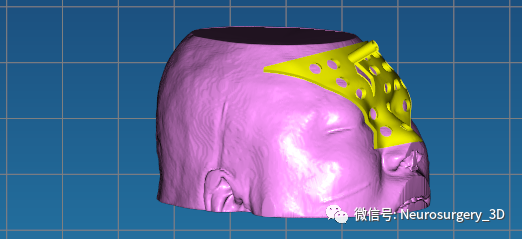

4、生成穿刺导板面具

5、修剪需要打印的穿刺导板

9、把生成穿刺导板面具的STL导入到Mimics软件中,应用Simulate剪切成规则需要模型。

10、把通过Mimics剪切后的穿刺导板再以STL格式保存到桌面上。

11、穿刺导板镂空:把Mimics剪切后的导板导入E3D软件界面,进行镂空处理后备用。

12、手术消毒备用.....